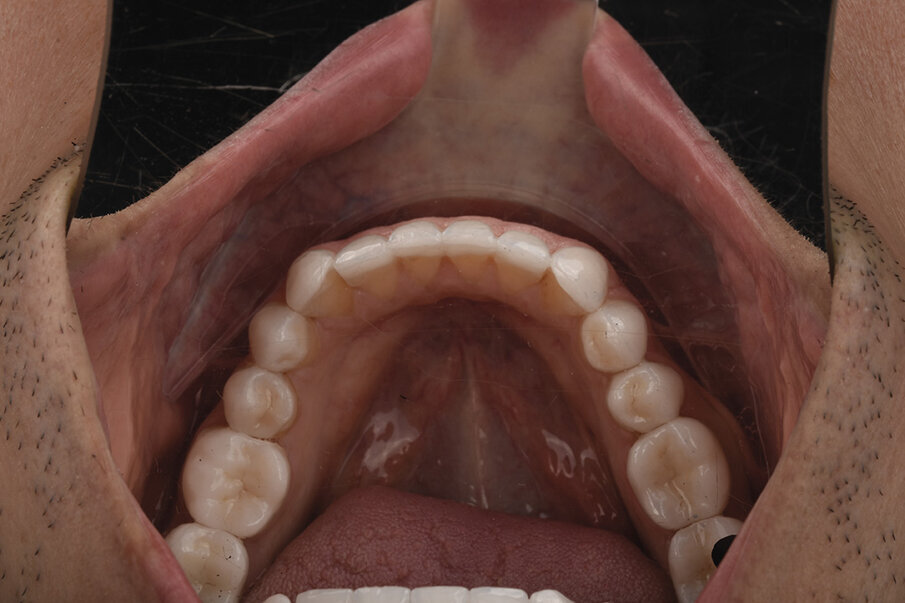

4. Ekstraoralni i intraoralni fotoprotokol (Sl. 1- 4).

5. Skeniranje zuba

-Intra oralni sken inicijalne situacije

-Intra oralni sken na zadatu, željenu visinu pomoću jig-a (Sl. 5)